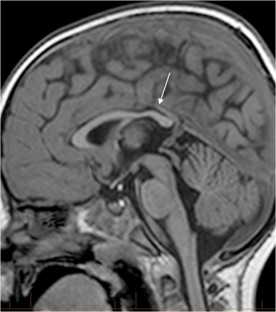

We selected pediatric head MRI examinations from 2005 to 2017 based on the finding of a double midline sellar and suprasellar bright spot on T1-weighted sequence. Medical history, physical examination, pituitary hormonal profile and bone age evaluation were extracted from the medical record of the selected patients. An experienced pediatric neuroradiologist reviewed head MRIs, which were performed on 3-tesla (T) magnet and included at least sagittal T1-weighted imaging centered on the sella turcica obtained with and without fat suppression.

In six cases, two midline bright spots were identified on T1-weighted sequences obtained both with and without fat suppression. While one spot was located at the expected site of the neurohypophysis in the posterior sella, the second one was in the region of the median eminence, suggesting partial ectopic posterior pituitary gland. Growth hormone deficiency, either isolated (n=1) or combined with thyroid stimulating hormone deficiency (n=1) was found. None of the children had clinical signs of posterior pituitary dysfunction.